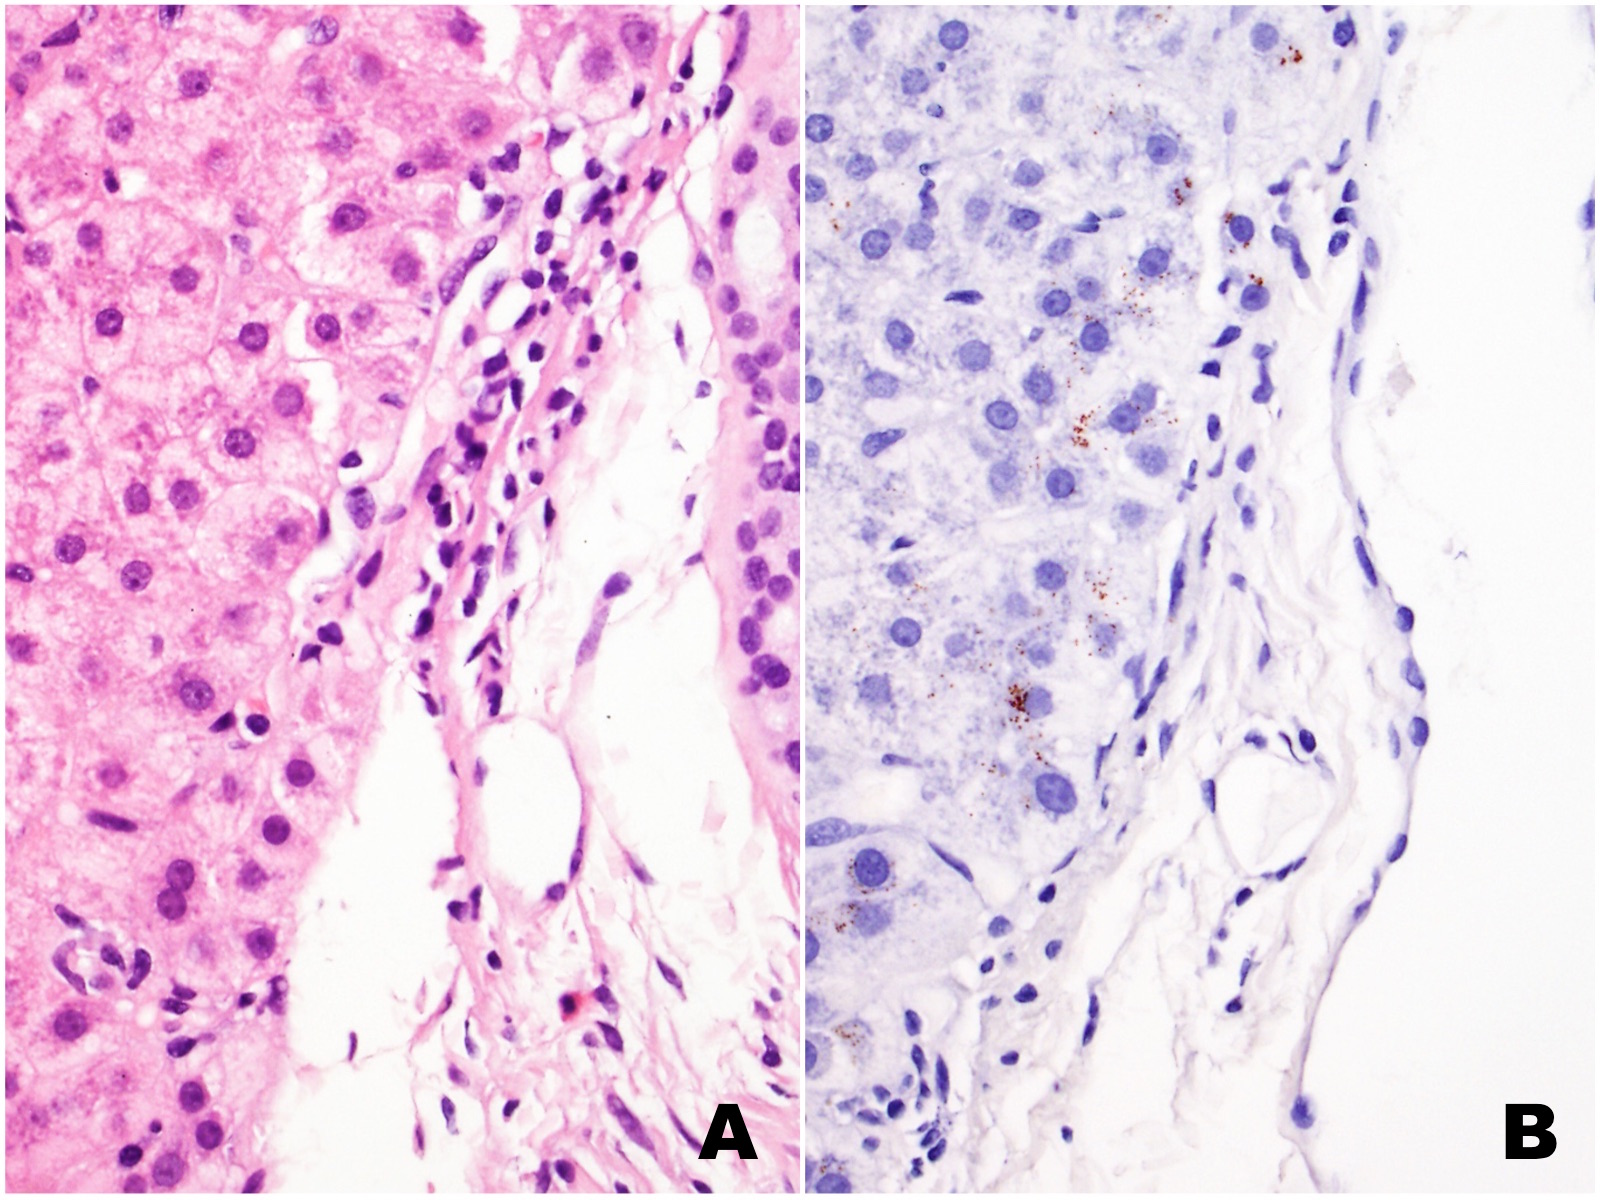

The liver biopsy shows extensive sinusoidal infiltration by bland appearing plump eosinophilic cells with somewhat retractile or granular cytoplasm (Figures 1A and 2A). These cells are positive for CD68 confirming they are histiocytes (Figures 1B and 2B). The histiocytes contain crystalline immunoglobulin kappa highlighted on the Ig kappa and PAS-D stains (Figures 3A and 3B, respectively). Ig lambda was negative.